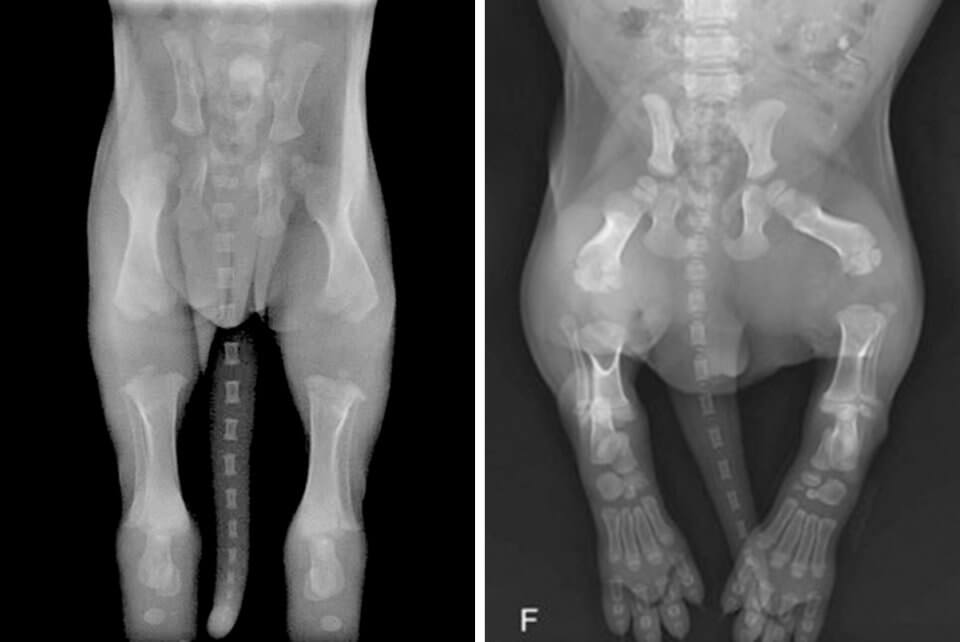

Adekvatna fizička aktivnost, primerena uzrastu i stepenu razvijenosti organizma, je neophodna za zdravlje i pravilan razvoj pasa, kao i ljudi. Prekomerna ili previše intenzivna fizička aktivnost može dovesti do ozbiljnih povreda, posebno kada su u pitanju štenci, kod kojih kosti i zglobovi nisu u potpunosti razvijeni.

Fotografija 1: rendgenski snimak karlice šteneta, izvor: https://www.instituteofcaninebiology.org/blog/archives/12-2015

Fotografija 2: rendgenski snimak karlice steneta starosti 34 dana, izvor: https://veteriankey.com/radiographic-considerations-of-the-young-patient